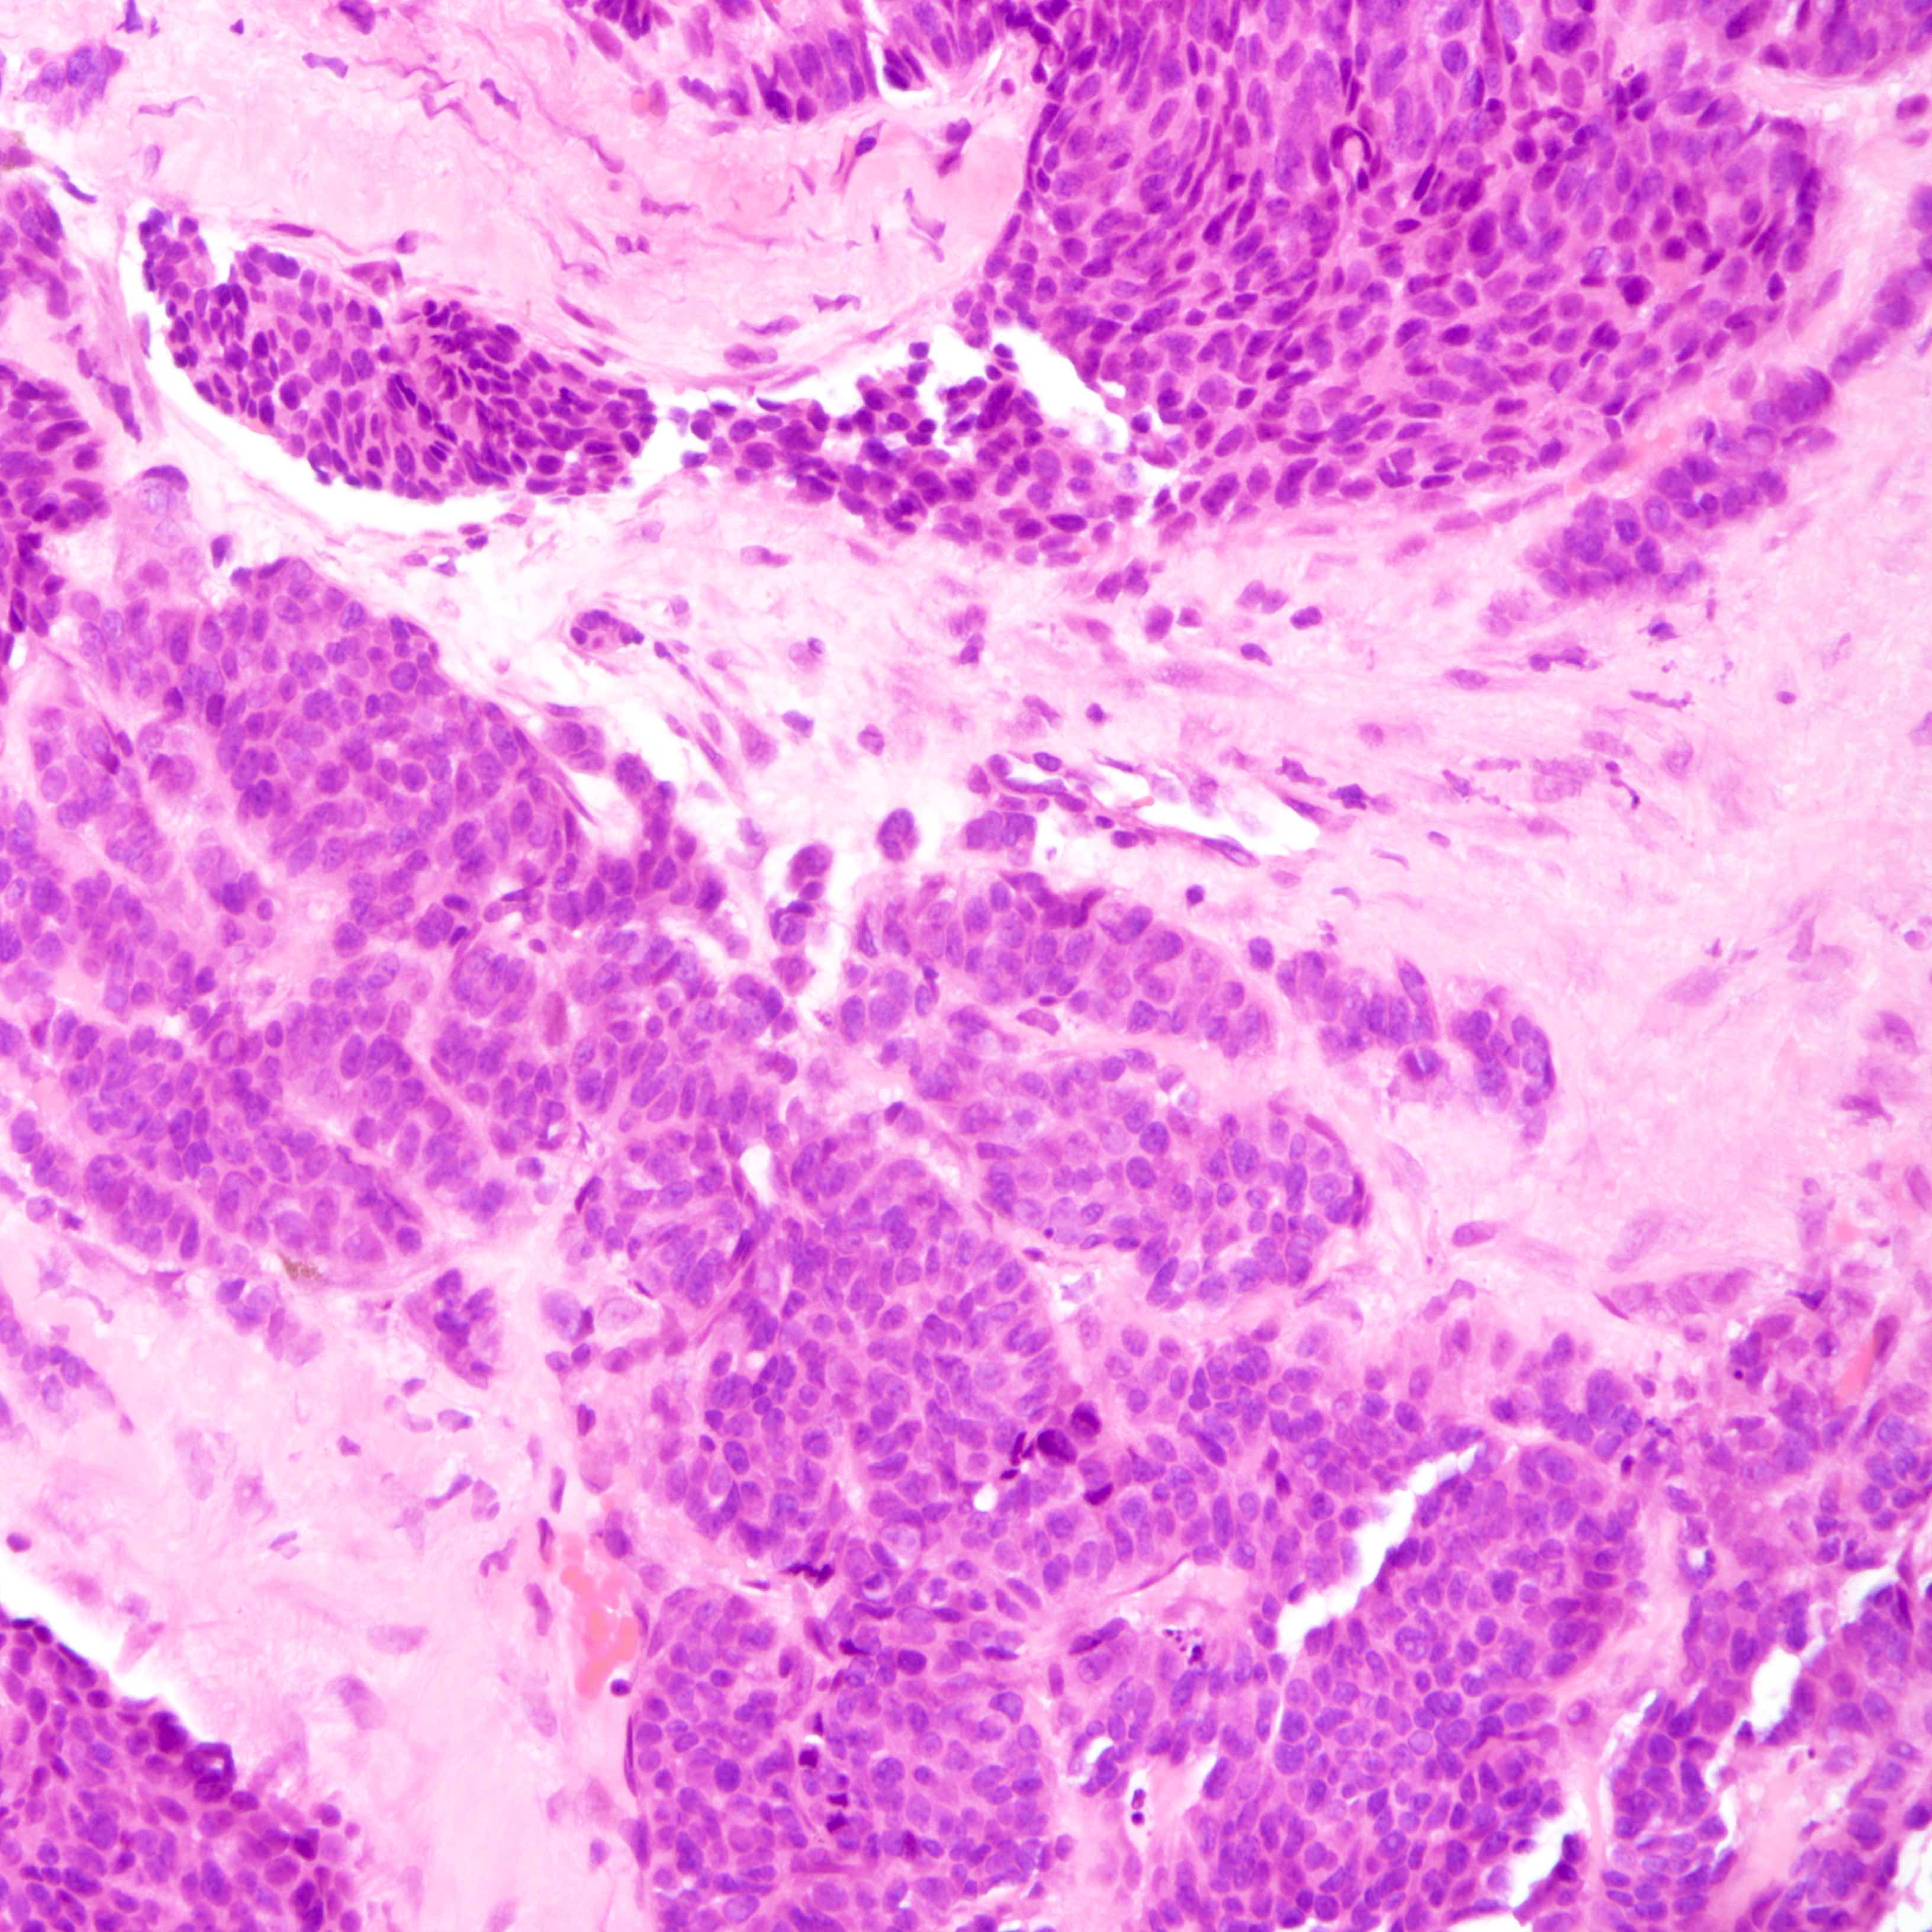

Contributed by Joshua J.X. Li, M.B.Ch.B., Gary M. Tse, M.B.B.S. and Kristen E. Muller D.O.

Small cell carcinoma

- Small cell carcinoma:

- Infiltrative growth pattern

- Crush artifact frequent

- Necrosis and lymphovascular invasion common

- Tumor cells densely packed with ill defined cell borders

- High N/C ratio with scanty cytoplasm

- Small dark hyperchromatic nuclei and inconspicuous nucleoli

- Mitotic count high

- Associated with proliferative changes, in situ carcinomas and invasive carcinomas (Am J Surg Pathol 2000;24:1231)

- In situ small cell carcinoma present in 5 out of 9 cases in a case series

- In situ / invasive ductal, lobular and squamous neoplastic components occasionally identified

- Infiltrative growth pattern